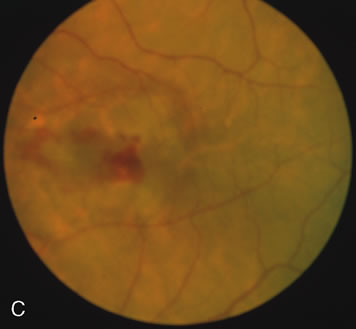

Of more clinical importance is the role of FA in the diagnosis and treatment of cystoid macular edema (CME) (Fig. 1C and D). Stereoscopic FA indicates that the leakage, which may be diffuse or have the typical petaloid stellate appearance of CME, can come from the perifoveal retinal capillaries, from the choroid through the RPE, or from a combination of both sources.4 With the recent suggestion that CME in RP may be successfully treated with acetazolamide,5, 6 FA is thus important to document the diagnosis of CME, establish the origin(s) of leakage, and follow patients during and after therapy.